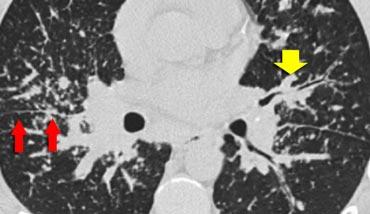

Ca lâm sàng 1

Hình ảnh cho thấy một trường hợp điển hình của phân bố nốt quanh bạch mạch ở bệnh nhân sarcoidosis.

Lưu ý các nốt dọc theo khe liên thùy (mũi tên đỏ), gợi ý phân bố quanh bạch mạch.

Việc kiểm tra cẩn thận các nốt này ở vùng dưới màng phổi và dọc theo khe liên thùy là cần thiết, vì đây là dấu hiệu có độ đặc hiệu cao cho sarcoidosis.

Thông thường, sarcoidosis biểu hiện ưu thế ở thùy trên và vùng quanh rốn phổi, với phần lớn các nốt nằm dọc theo bó phế quản-mạch máu (mũi tên vàng).